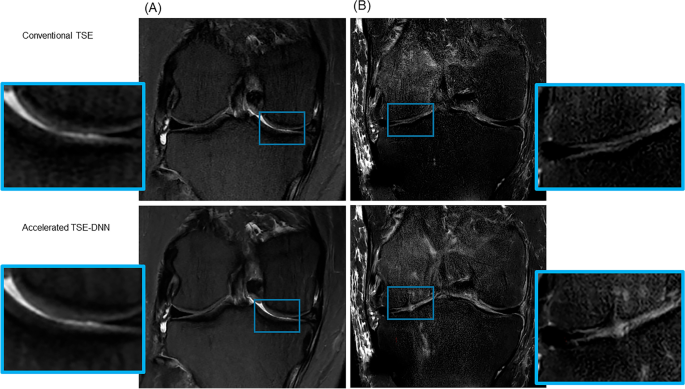

All FSE-conv and FSE-DNN images were rated of lesion detection by three interpreting musculoskeletal radiologists. In evaluation of lesion detection, the diagnostic performances of FSE-DNN showed comparable results in ligamentous, meniscal, and cartilaginous lesions (Table 3, Fig. 6). Two of cartilage lesions was under-graded or over-graded (n = 2) while there was no significant difference in other image sets (n = 43). Representative imaging examples for cartilage under-grading or over-grading are shown in Fig. 7.

Cartilage grade on conventional and reconstructed images of accelerated sequences. (A) A 54-year-old female with knee pain. Cartilage fissuring is shown in medial femoral condyle (upper A) while the cartilage fissuring is smoothened, showing under-grade chondromalacia on 2D FSE-DNN image (lower A). (B) A 41-year-old male with knee pain. Cartilage signal changes without significant defect in lateral tibial plateau (upper B) while the cartilage showed T2 high signal intensity defects on 2D FSE-DNN image, showing over-graded cartilage (lower B).

In the diagnostic performance of lesion analysis, FSE-DNN reconstructed images showed non-inferiority compared to FSE-conventional images. In our study, no significant difference was observed in the diagnostic performance between FSE-conventional and FSE-DNN images. In cartilage evaluation, FSE-DNN showed under-graded lesion (n = 1) and over-graded lesion (n = 1) in small numbers (n = 2/45) among 45 image sets. However, there is no statistical difference between FSE-DNN reconstructed images and FSE-conventional images in this 45-case study. This under-grade or over-grade of cartilage may have originated from acceleration artifacts and image degradation rather than the DNN- reconstruction in our early clinical validation with routine clinical MRI protocols (Fig. 7). Cartilage under-grading on FSE-DNN could also have been affected by the amount of image denoising. This suggests the need for careful selection of acceleration method and denoising settings for cartilage imaging, which may depend on imaging target structures. Conversely, cartilage could be over-graded from parallel imaging-related artifacts. In an under-graded chondromalacia case, cartilage fissuring was smoothened on FSE-DNN images while cartilage signal was slightly enhanced in an over-graded chondromalacia case. This highlights the necessity for MRI sequence optimization, particularly emphasizing the need for more precise learning when it comes to small structures like cartilage and structures influenced by MR signal intensity. This acceleration optimization could be different depending on the target joint (e.g. a large off-center shoulder and a small extremity hand) and target structures such as ligaments, bone marrow, meniscus, and cartilage. Further study involving a larger number of images is needed to validate this aspect.